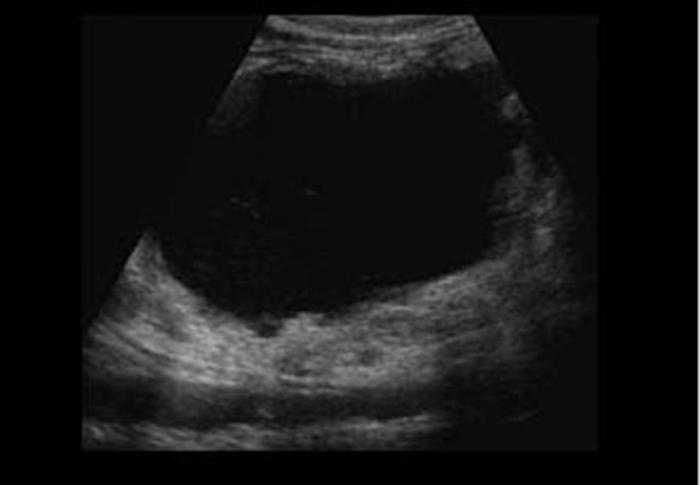

Hydrops GB

Greater than 4cm in diameter